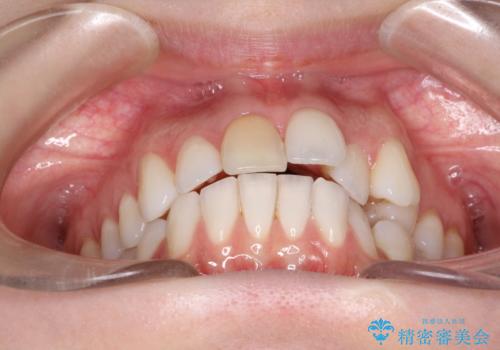

インビザラインによる非抜歯での八重歯の矯正

- 左上の八重歯と、上の歯のがたつきを主訴に来院されました。

上の奥歯を後方に移動させてスペースを作るのと、歯と歯の間をわずかに削り歯を並べる計画としました。